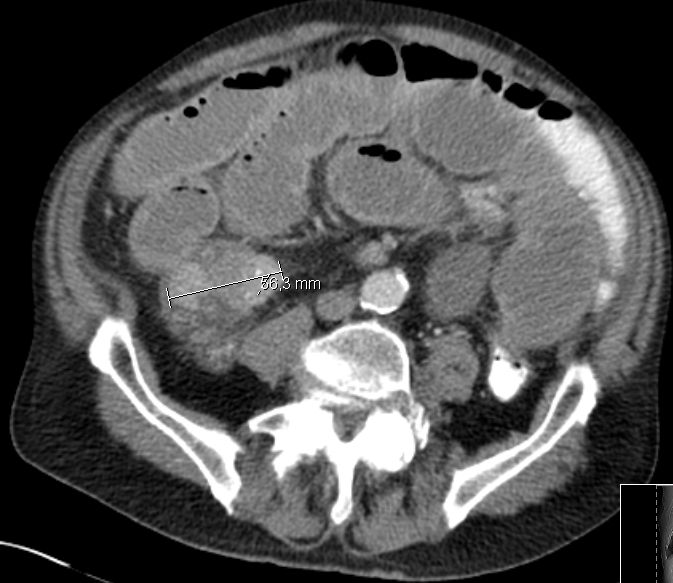

Colon 79-jährige Frau mit einem Tumor im Zoekum. Bei der Operation fand sich im Bereich der Ileozökalklappe ein unregelmäßig gestalteter, teils ulzerierter und teils polypös erhabener, 42 mm großer, derber Gewebsbezirk. Histologie: In soliden Komplexen und Strängen angeordnete, relativ große Tumorzellen mit deutlicher Zell- und Kernpolymorphie. Vergrößerte Zellkerne mit aufgelockerter Chromatinstruktur und ab und an prominenten Nukleolen. Schmaler oder kaum erkennbarer Zytoplasmasaum. Vermehrt typische und atypische Mitosen. Tumoreinbruch in Blut- und Lymphgefäße. Das CT zeigt multiple Lebermetastasen.